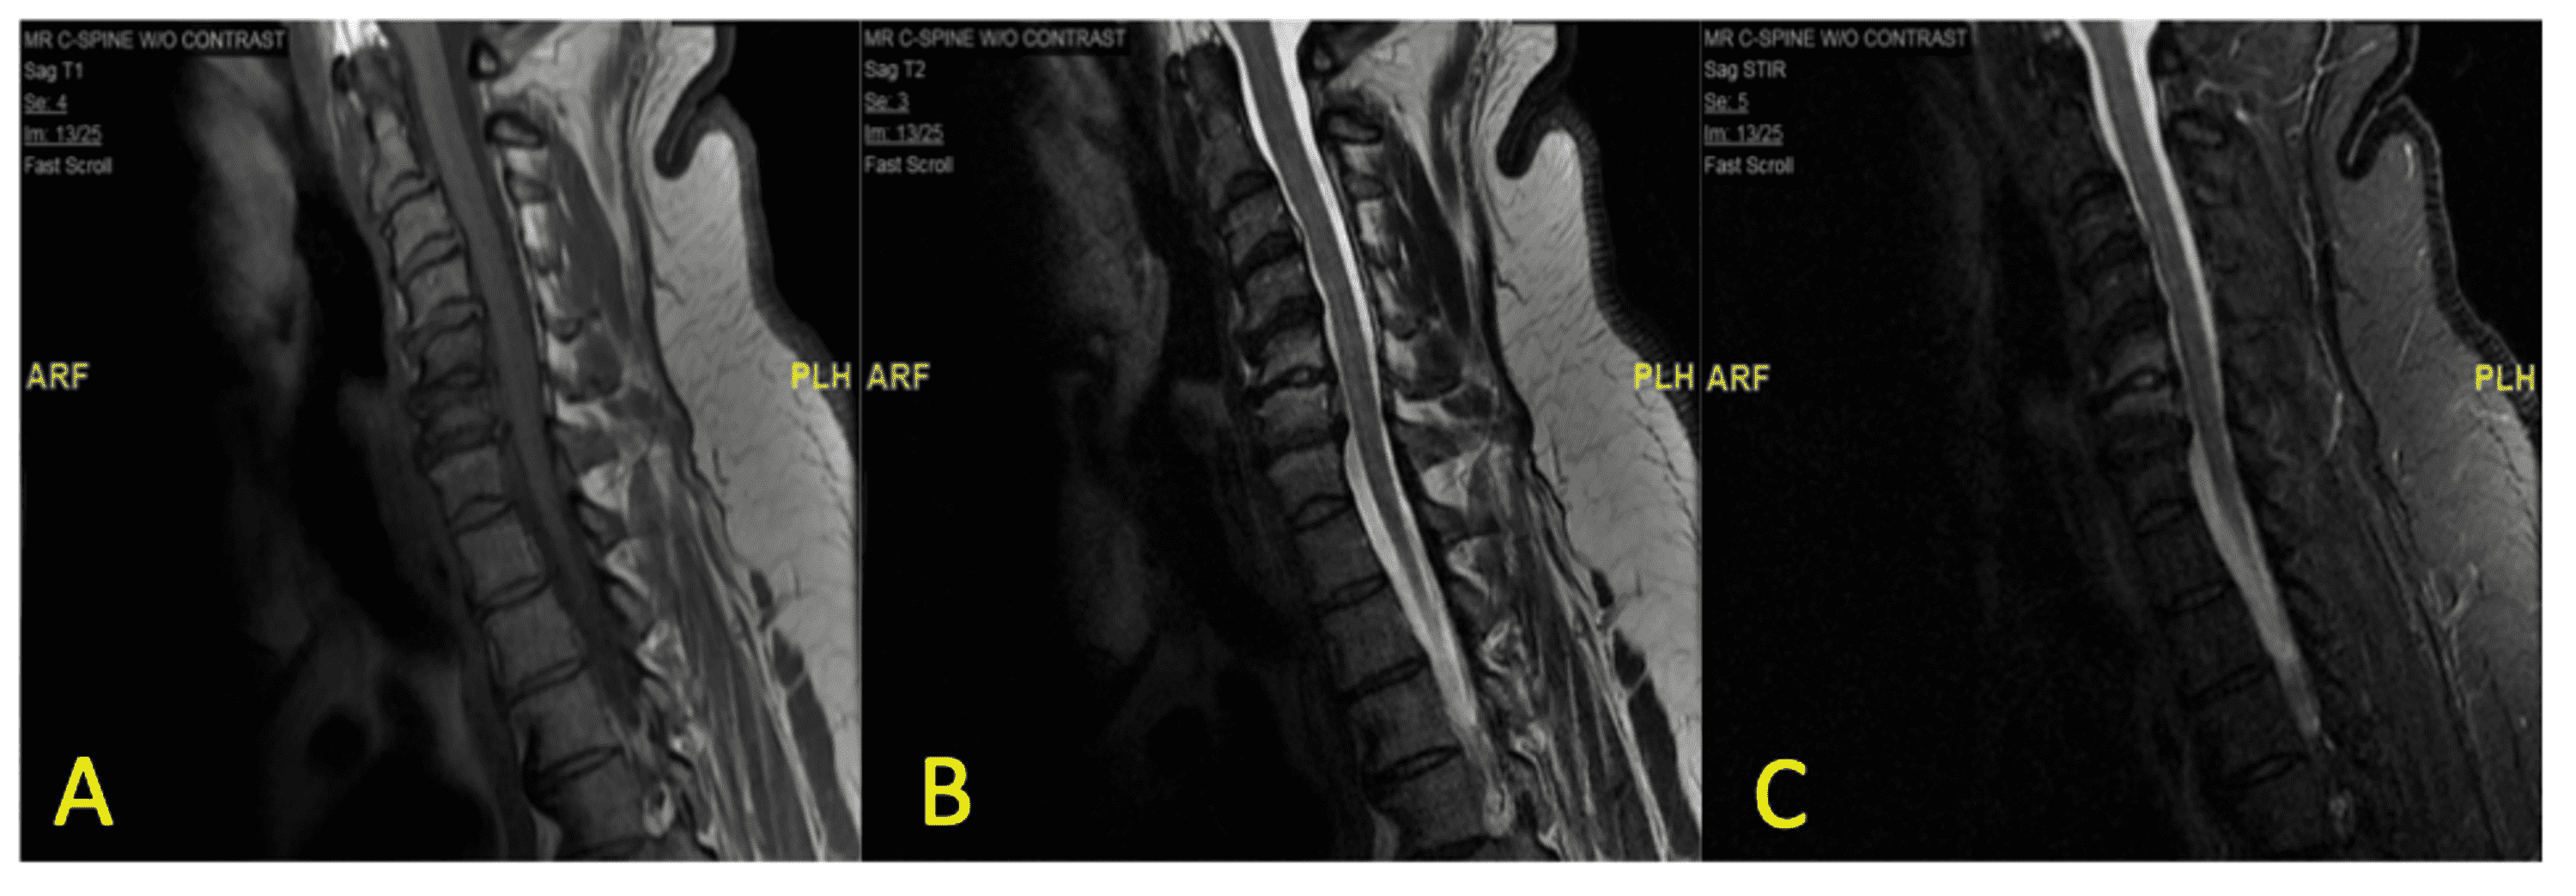

Cervical vertebrae osteomyelitis Radiology Cases